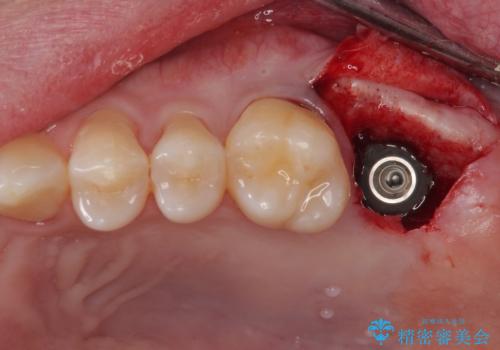

- 他院で虫歯治療の途中の歯を治療したいとのことで来院された患者様です。来院時特に症状もなく、根管治療途中の状態でした。レントゲン上でも大きい病変を認めました。治療方針として再度根管治療を行うか、抜歯をしてインプラントにする二つの方法をご提案しました。

咬み合わせが強く根管治療後の歯の破折のリスクや治療期間の観点からインプラント治療を行っていくこととなりました。

根尖病巣も大きかったため先に抜歯を行い、1ヶ月後にインプラントを埋入しました。

インプラントの埋入から被せものの装着まで2ヶ月で終えることができました。治療期間も短く、しっかり咬めるため大変喜んでいただきました。